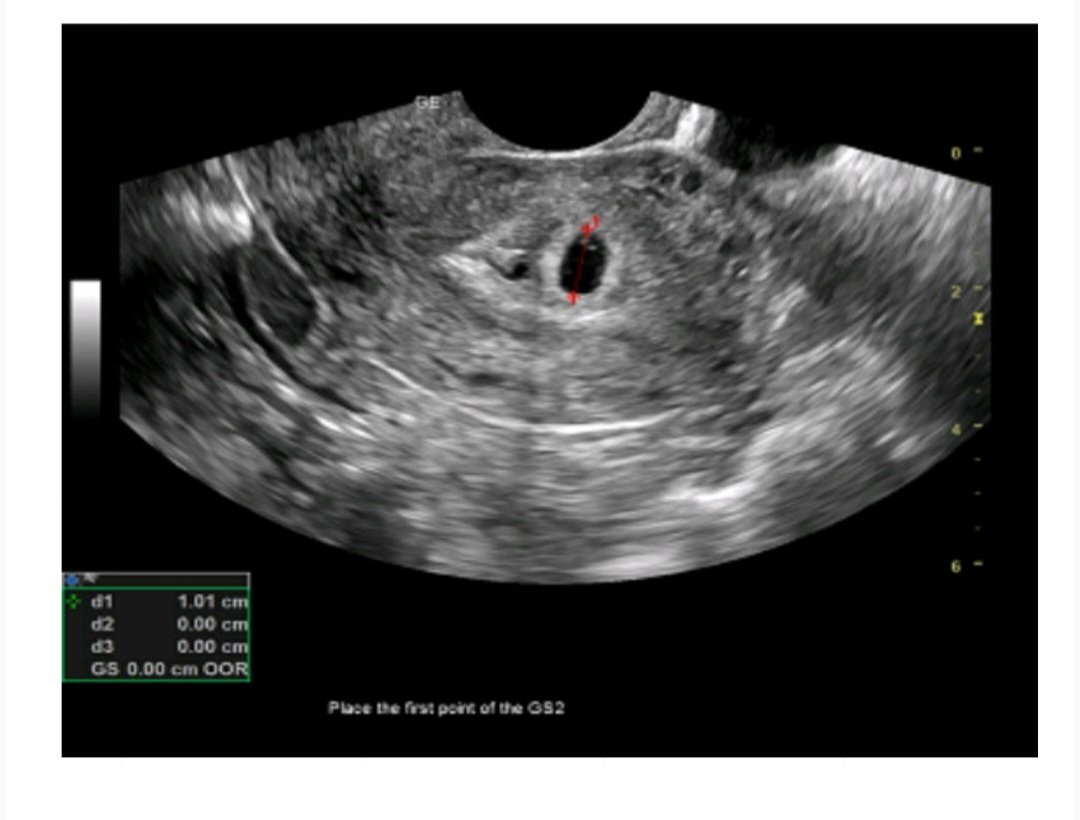

В 4г.с съм, гестационният сак е 10 мм. и се визуализира и жълтъчно мехурче. Казаха ми да дойда след около 2 седмици, за да чуем и сърдечния ритъм.

Предупредиха ме, че може да имам евентуално кървене, но да не се притеснявам.

Ще се радвам да чуя и второ мнение и не разбирам кое точно е жълтъчното мехурче и каква е тази малка черна точка в ляво - това ли е мехурчето? Благодаря!